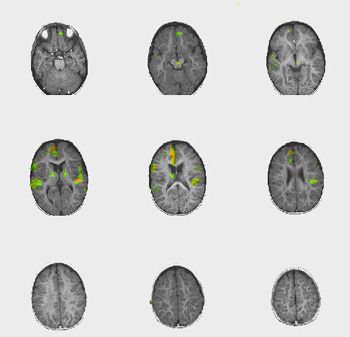

Case 1

| Patient | 2 month-old-girl with hydrocephalus | ||||||

| Paradigm | ON: Presentation of mother's voice, pre-recorded, using familiar words OFF: Nothing. Patient sedated with chloral hydrate | ||||||

| Statistics |

| ||||||

| Activation | There is bilateral activation of the precentral gyri and the right superior temporal gyrus. The activation of the motor strip occurs at the level of oral-facial representation. This is supposed to be related with the habituation-dishabituation of high-amplitude sucking in response to lingustic stimuli. This response is of great importance in the preservation of our species. | ||||||